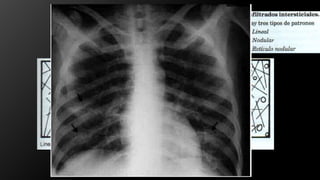

Infiltrados Pulmonares:

• Grupo de opacidades que aparecen donde normalmente existía transparencia

pulmonar. Son imágenes radiopacas que aparecen donde normalmente había imágenes

radiolúcidas.

• Los que comprometen el espacio aéreo, que son los infiltrados de tipo alveolar.

• Los que comprometen el intersticio que son los infiltrados intersticiales.

Infiltrado retículo-nodular